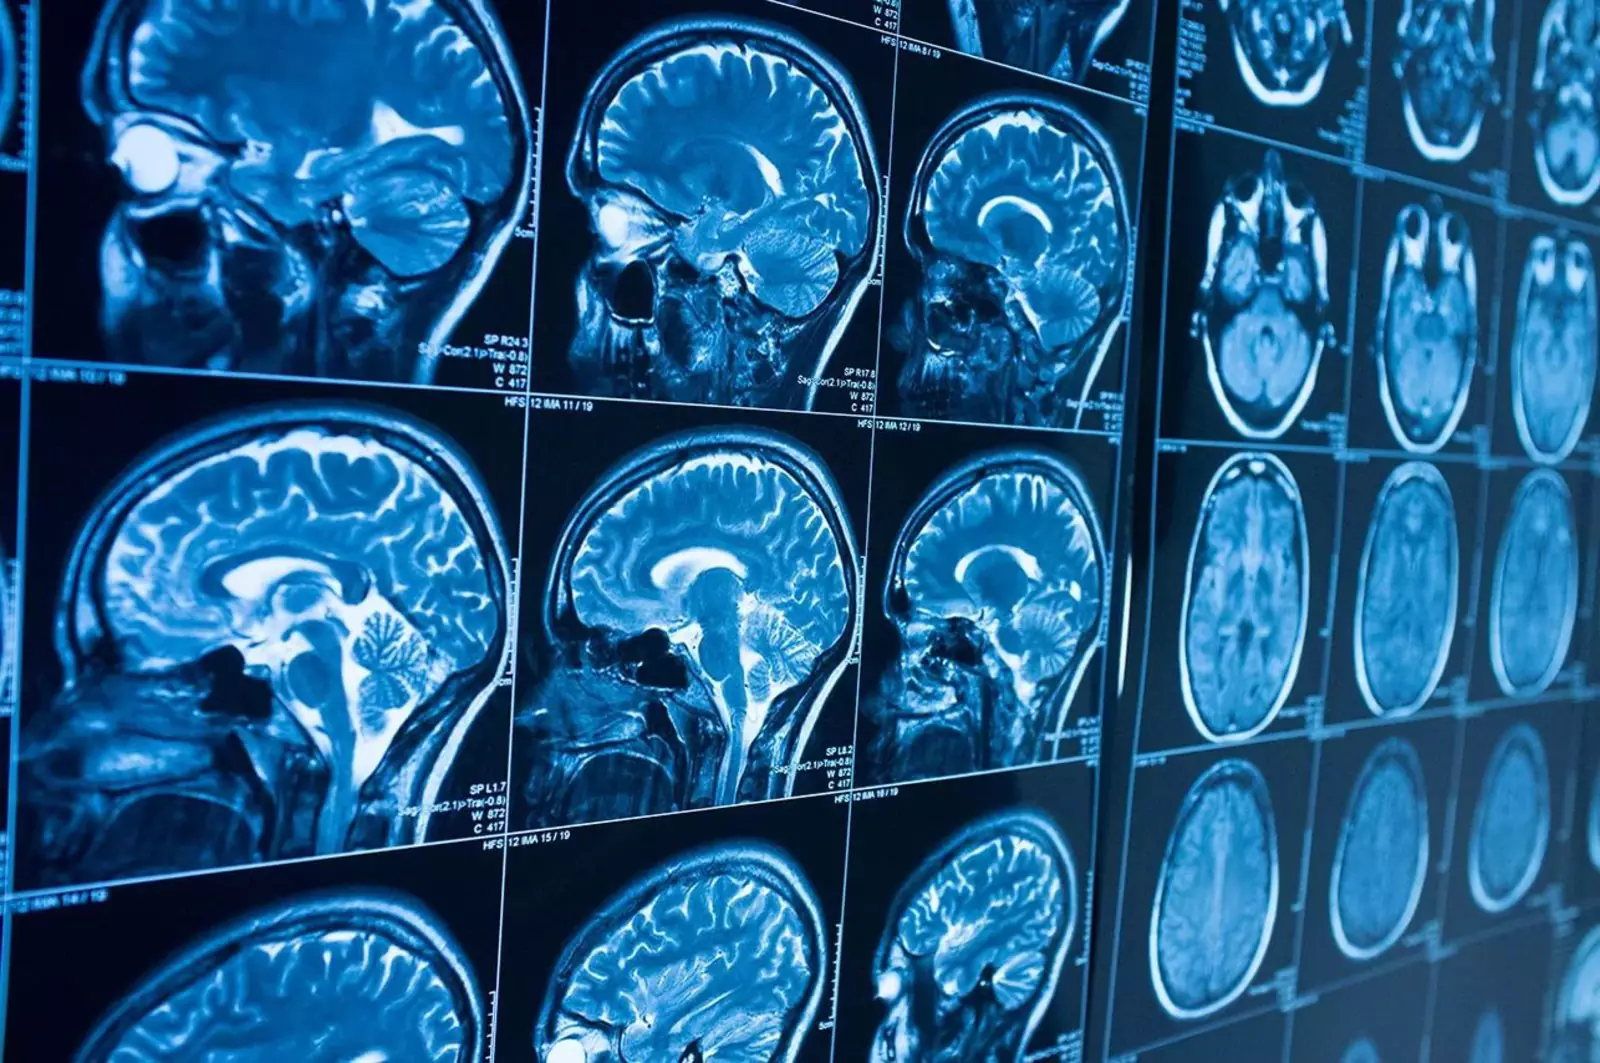

Чтобы лучше понять взаимосвязь между травмой головы и зависимостью, команда Ютса изучила снимки мозга 34 человек, которые внезапно потеряли желание курить после инсульта или ранения. После этого исследователи сравнили эти снимки с данными 69 курильщиков, которые продолжили курить после черепно-мозговой травмы.